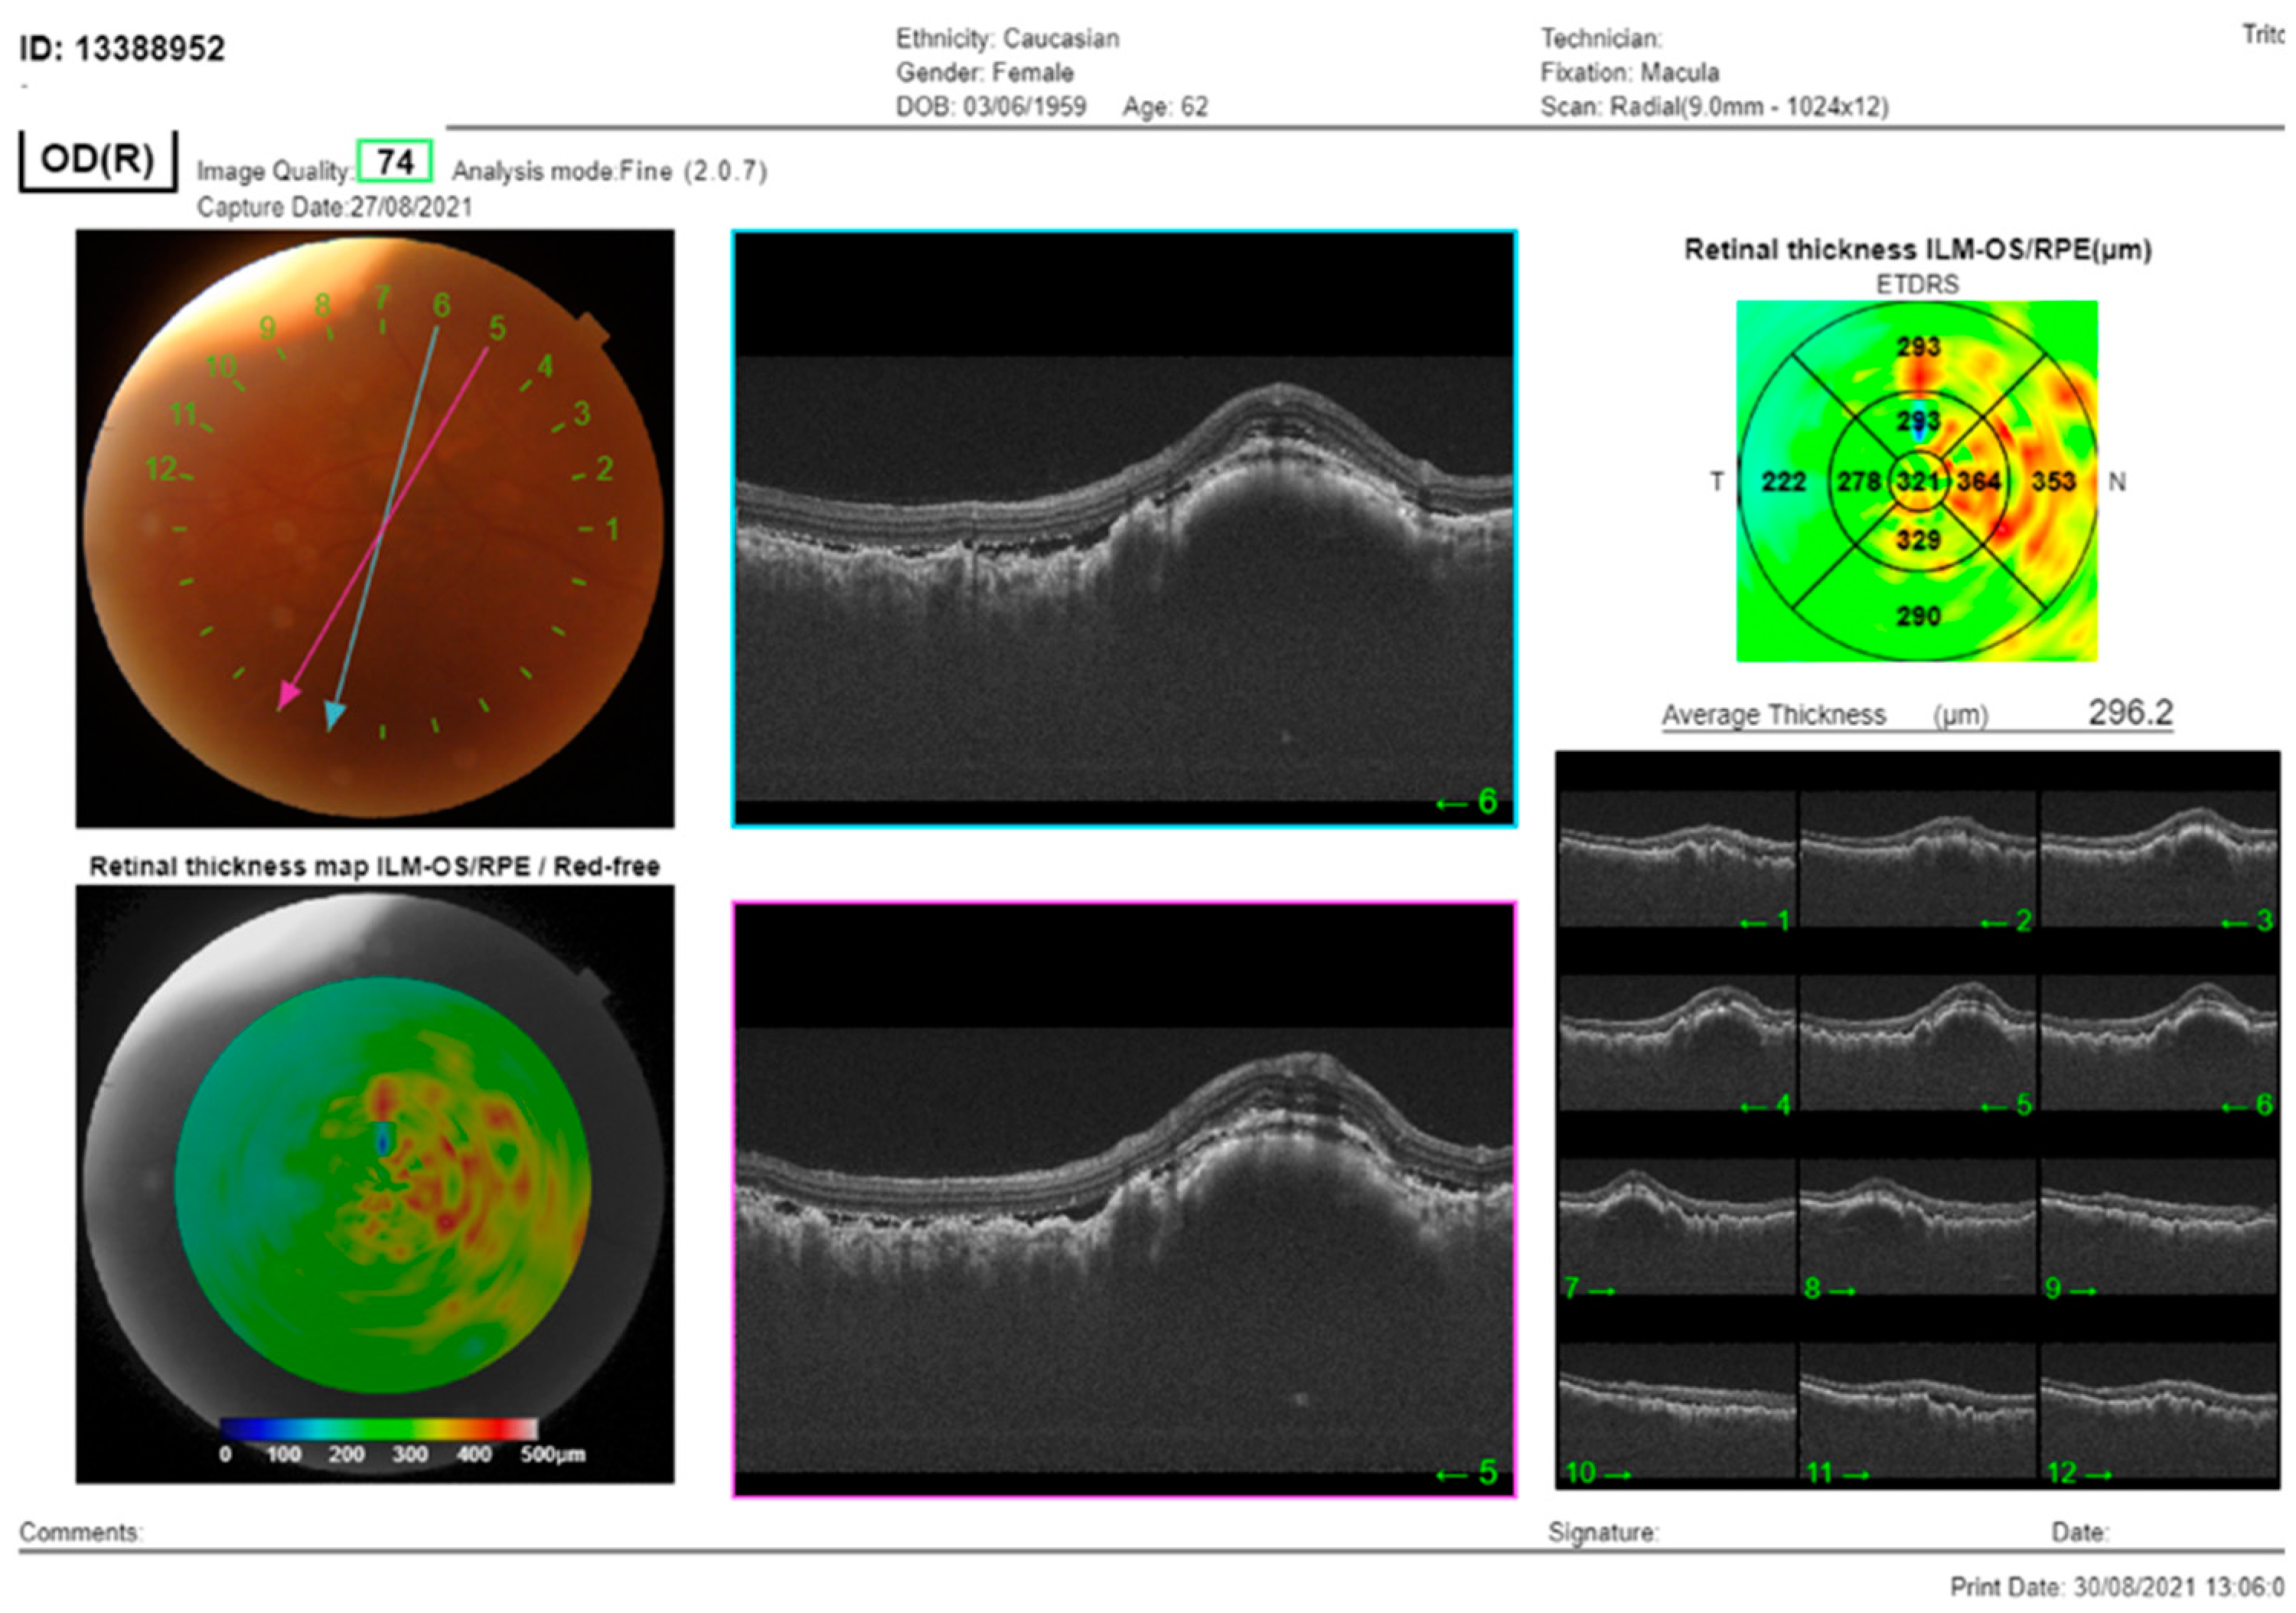

In the right eye, the OCT signal was notably weakened by the presence of dense cataracts. Nevertheless, despite this impediment, subretinal fluid and choroidal thickening were both still evident in this eye (Figure 2).

Figure 2. The SS-OCT (DRI OCT Triton, Topcon Co, Tokyo, Japan) showed choroidal thickening with overlying folds and subretinal fluid. OCT of the macula of the RE: cross-section through the lesion showed thickening of the choroid, with subretinal fluid and overlying folds of RPE.